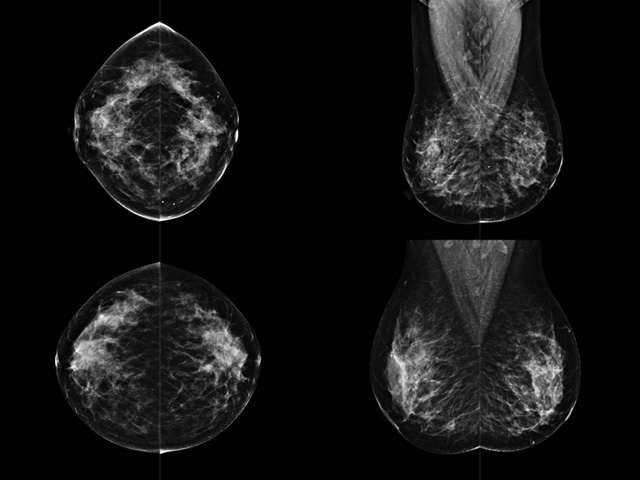

乳房檢查時候要注意一些細節(jié),需要更深入的了解這樣才能使檢查更準確。乳腺DR是乳腺癌的篩查診斷工具設備。是乳房方面檢查的重要影像方法。它可以臨床檢查出早期的乳腺癌。可以判斷良性惡性。因為它可以檢查出早期的病變。對良性惡性檢查的準確率達到90%以上。發(fā)病高峰年齡為45歲到54歲。50歲檢查出來乳腺癌病患,可以讓死亡率下降3成。所以30-40歲女性每年做一次乳腺DR檢查。40歲以上就一年兩次。如果家族史有乳腺癌的30歲以下也需要做檢查。清晰顯示乳腺各層組織嚴重的乳腺增生,乳腺炎,乳腺外傷也建議1年檢查一次。極大提高了早期乳腺癌的敏感度和診斷率。

大角度、高質量的乳腺檢查,可以讓女性帶來身體健康安全。為醫(yī)生提供了高清影像數(shù)據(jù)。乳腺檢查時候各個部位影像顯示出來。白色乳腺導管跟纖維結締組織。模糊的是脂肪。病變一般是不透明的白色。有需要放大來檢查。乳腺DR沒有重疊偽影。輻射劑量更少。因為乳腺癌發(fā)病每年都有所提高,對女性都造成了嚴重的身體健康危害。早做檢查早治療是不可忽視的舉措。可以大大的降低死亡率。保證身體健康。一般檢查避開經期,來完7天左右是最佳的檢查時間。絕經的女性就沒有要求。孕婦不參加乳腺DR檢查, 6個月內準備妊娠的婦女也不宜行此檢查。